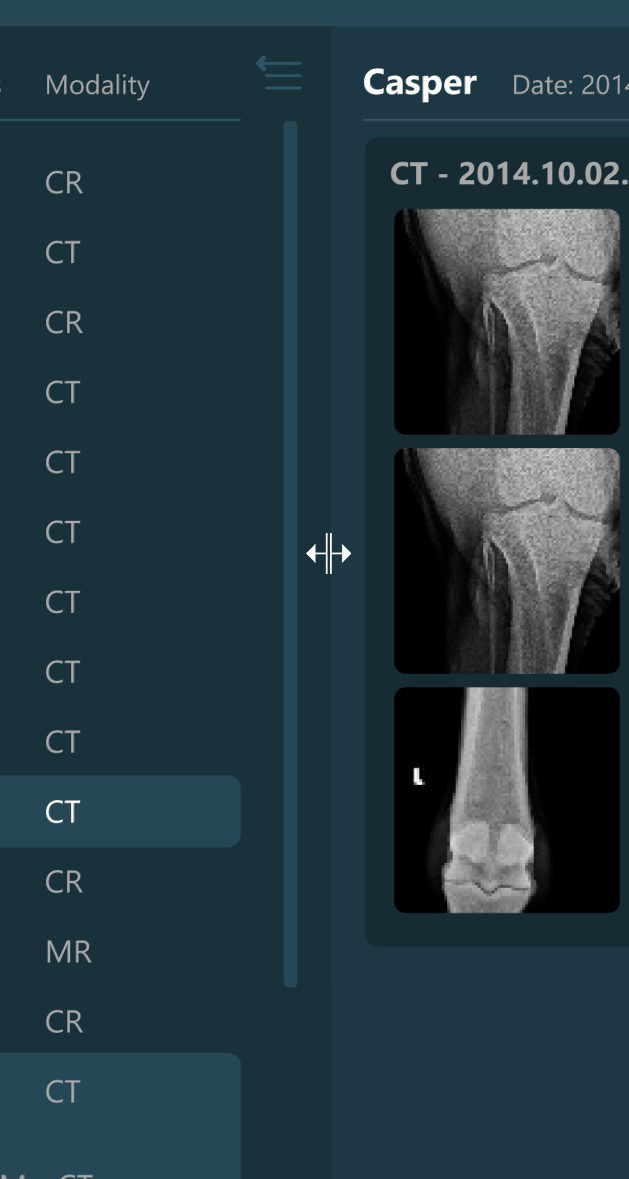

Selecting a patient, study, or series from the Study List opens them and their contents in the Preview Pane, located on the right side of the Study Browser window. In the Preview Pane, the items are separated into sections based on their patient information.

The heading of each section shows the patient name, the latest related study date, patient sex, and owner name. Studies are shown as image groups containing the series as image previews. Each study is highlighted by its modality and date. To view the series description of each series, hover over the desired image preview.

Similar to the selection in the Study List, users have the ability to select patients, studies, or individual series. A highlighted selection in the Preview Pane indicates the active selection in the Study List.

The Preview Pane can also be used to extend or narrow down the selection from the Study List. To select/deselect items in the Preview Pane simply press on them with the mouse.